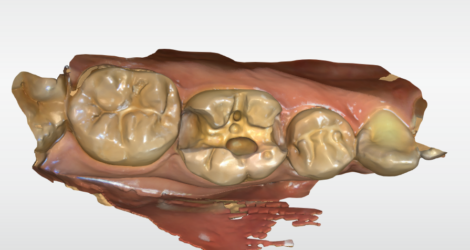

こんにちは!歯科衛生士の舘山です!

今回は歯ブラシしてる時に歯ぐきから出血があり痛くて磨けないという方にPMTCをした方になります。

治療前↓

こちらの写真はネクストビジョンという機器で撮影したものになります。口腔内カメラと顕微鏡の機能を兼ねたデジタルマイクロスコープで4Kで写真を確認することが出来ます☆